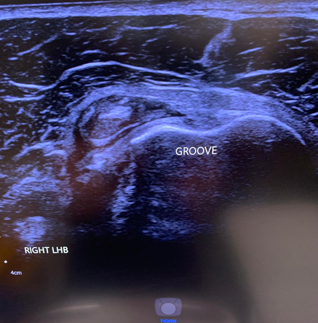

LHB subluxation can happen with contact sports, weight lifting and bodybuilding.

Sometimes the biceps tendon can pop out of its groove. This usually happens because of a tear of the overlying ligament. In other cases, some people are just born with a particularly shallow bicipital groove which puts the tendon at risk of subluxing under load.

Ultrasound findings are of a tendon that is not correctly sited in the bicipital groove (Red circle. The white circle shows where the LHB should sit). To find out more about LHB subluxation: